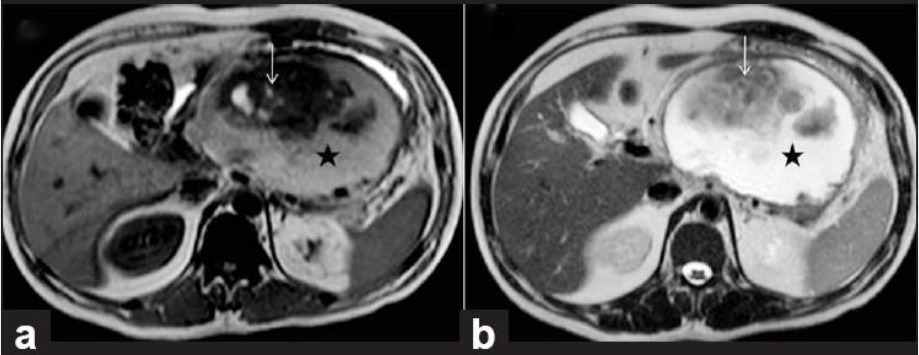

Q

מהו הממצא

A

IPMN

הרחבה של צינור הלבלב יחד עם ציסטה, מדובר בציסטה גידולית

How well did you know this?